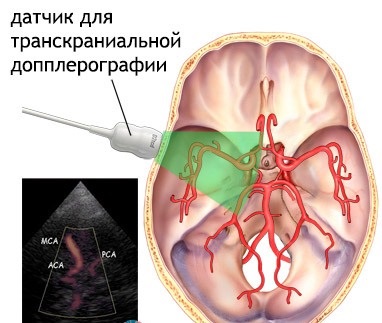

Az ugyanazon Doppler hajók a következőképpen működik: a jelátalakító (szenzor) bocsátanak ki ultrahang hullámokat előre meghatározott tulajdonságokkal rendelkezik, tükrözi viszont a sejtekben található a vérben, ami őket változtatni. Minden ugyanaz érzékelő méri a visszavert hullámokat, és rögzíti, hogy a különbségek kibocsátásra. Ezután az összes beérkezett információ feldolgozása és megjelenik a monitoron eszköz, ahol az orvos lehet az összes vizsgált és mért.

Doppler ultrahang a nyak hajók, és a fej két fő típusa van:

- Transcraniális. Ebben a vizsgálatban, a vérerek bekövetkezik diagnosztika, amelyek belül vannak koponyaüreg és közvetlenül táplálja az agy.

- Extracranialis. Ez Doppler vizsgálatok hajók a nyak, arc, stb más szóval - ezek a hajók, amelyek részt vesznek a vérellátás a fej és a nyak, de ki a koponyaüreget.